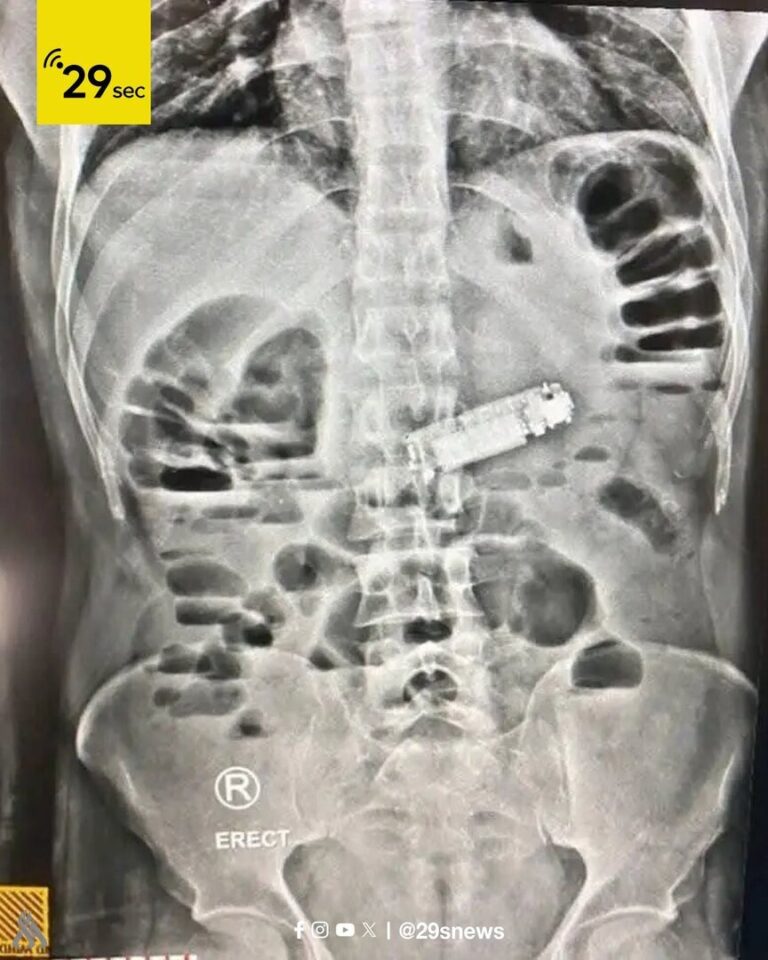

نجح فريق طبي متخصص في مستشفى الغردقة العام بمصر في إجراء عملية جراحية عاجلة لاستخراج هاتف محمول...